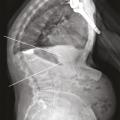

La présence de fractures incidentes augmente le risque de nouvelles ­fractures. Outre les douleurs, la ­multiplication des fractures vertébrales peut avoir des conséquences très délétères sur la statique rachidienne : perte de la lordose lombaire et augmentation de la cyphose thoracique. En particulier, les fractures de la charnière thoraco-lombaire, siège de prédilection des fractures ostéoporotiques, à la jonction d’un segment rachidien relativement fixe et d’un segment mobile, entraînent souvent une cyphose angulaire importante et préjudiciable sur le plan fonctionnel. Une seule fracture cunéiforme de la charnière thoraco-lombaire ou du rachis thoracique inférieur peut même générer 15 à 20° de cyphose, ce qui est loin d’être anodin.21 La cyphose vertébrale est un marqueur du vieillissement physiologique et un facteur de morbidité, du fait du déséquilibre sagittal du rachis, de la diminution des capacités fonctionnelles et respiratoire, de la majoration du risque de chute et donc de nouvelles fractures (fig. 6) ; elle accroît le risque de ­mortalité. La cyphose crée aussi un cercle vicieux mécanique : chaque fracture vertébrale l’accroît et majore le déséquilibre antérieur du rachis, la charge sur les autres vertèbres et donc le risque de nouvelle fracture. L’influence de la cyphose thoracique, sur le risque de fracture vertébrale incidente et sur la qualité de vie a été évaluée prospectivement sur 3 ans, dans une population de 1 624 femmes ménopausées ostéoporotiques non traitées.22 Une cyphose plus importante (quelle qu’en soit la cause) est un facteur de risque important et indépendant de nouvelle fracture vertébrale et d’altération de la qualité de vie.22 On sait aussi, depuis de récentes études épidémiologiques, que les fractures vertébrales ostéoporotiques sont associées à une surmortalité.23

Les fractures vertébrales ostéoporotiques ont tendance à se multiplier et à s’enchaîner, non seulement dans le temps, mais aussi dans le même segment rachidien, aggravant les déformations (fig. 7A et B). Dans une cohorte de femmes, d’âge moyen 74 ans, ayant une fracture vertébrale ostéoporotique récente, le risque de nouvelle fracture vertébrale dans l’année qui suit augmente de 3,6 %, si la patiente n’a aucune fracture vertébrale prévalente, à 24 % si elle a au moins deux fractures vertébrales prévalentes.24 L’âge, le caractère spontané de la fracture, la ­densité minérale osseuse, mesurée par ostéodensitométrie, les antécédents personnels et familiaux combinés dans le score FRAX25, le siège de la fracture, à la charnière thoraco-lombaire, et surtout le nombre de fractures vertébrales prévalentes permettent de prédire, dans une certaine mesure seulement, la survenue de nouvelles fractures vertébrales.